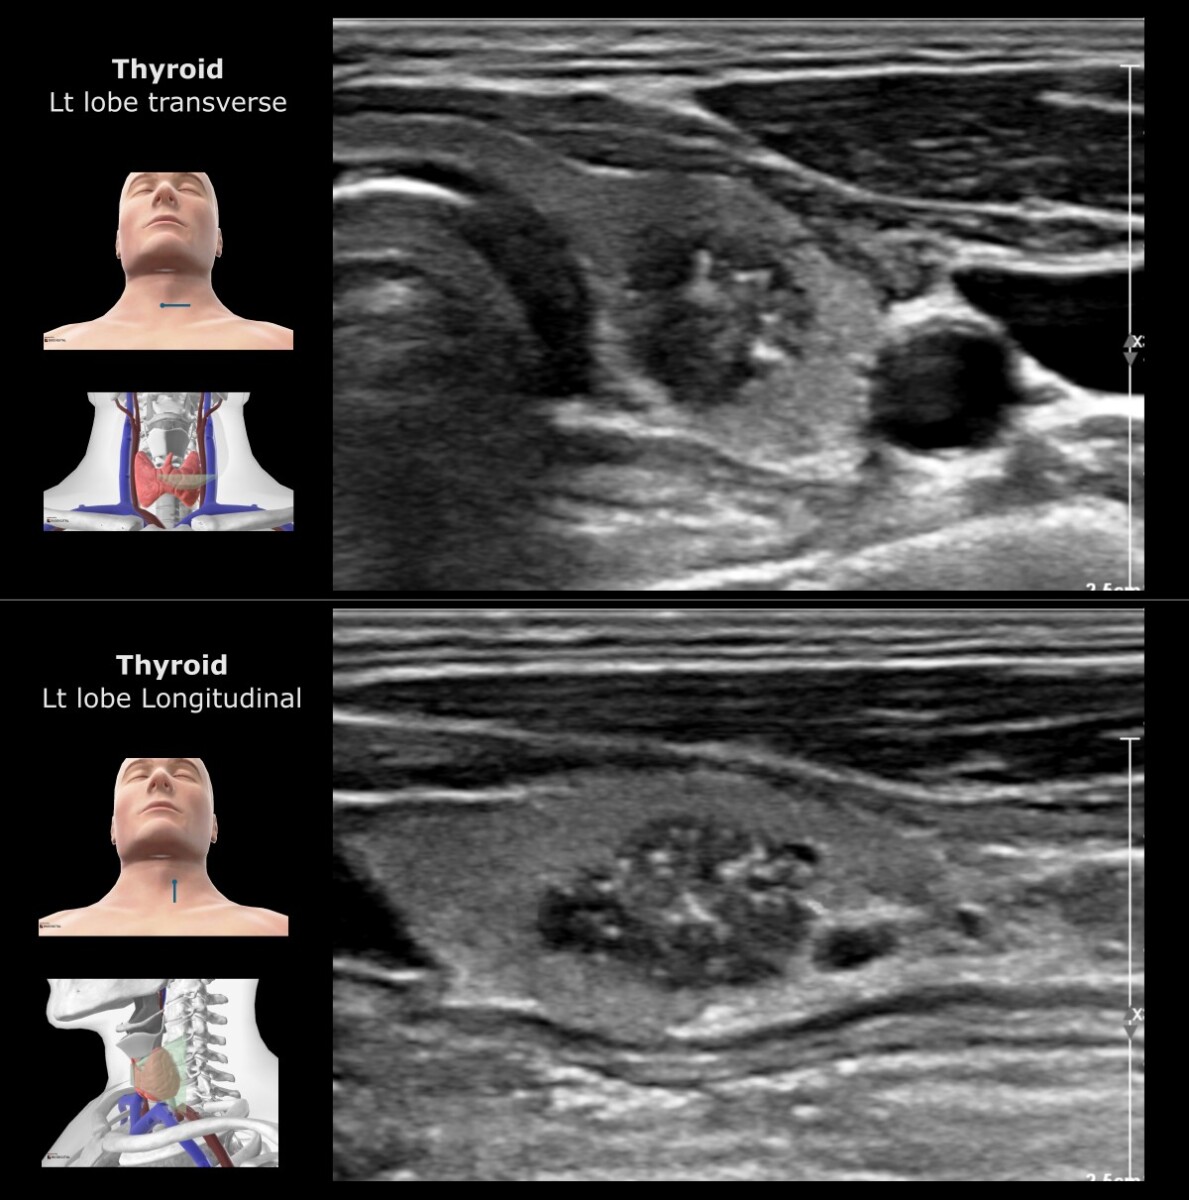

במקרה זה ניתן להסתכל על רקמת הבלוטה המקיפה את הקשרית ולהבין כיצד נראית רקמת בלוטת התריס באופן תקין.